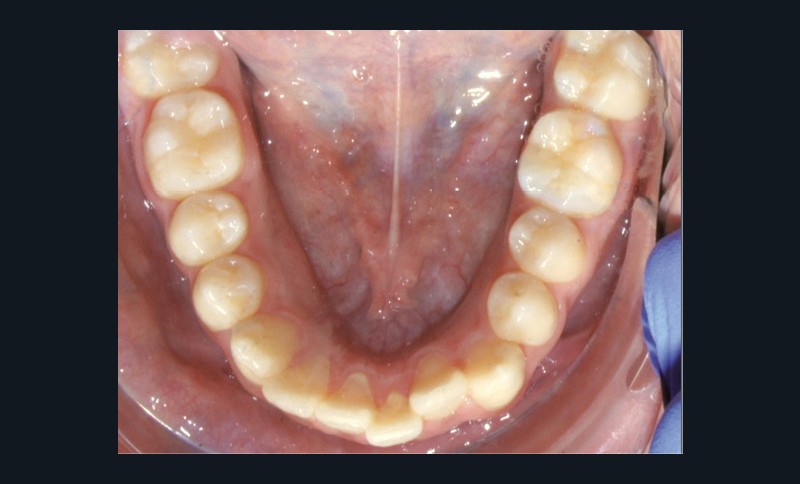

Examen endo-buccal (fig. 2a-e)

L’arcade mandibulaire est également parabolique avec un encombrement antérieur se traduisant par la vestibulo-position de 31 et la linguo-position de 32. L’encombrement est de 3 mm.